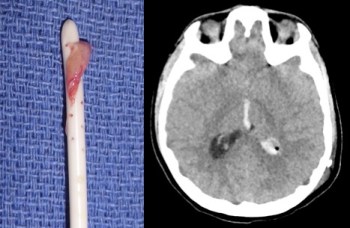

cathéter ventriculaire et sa gaine - d’un engainement ventriculaire cicatriciel avec un fonctionnement positionnel ou à éclipses